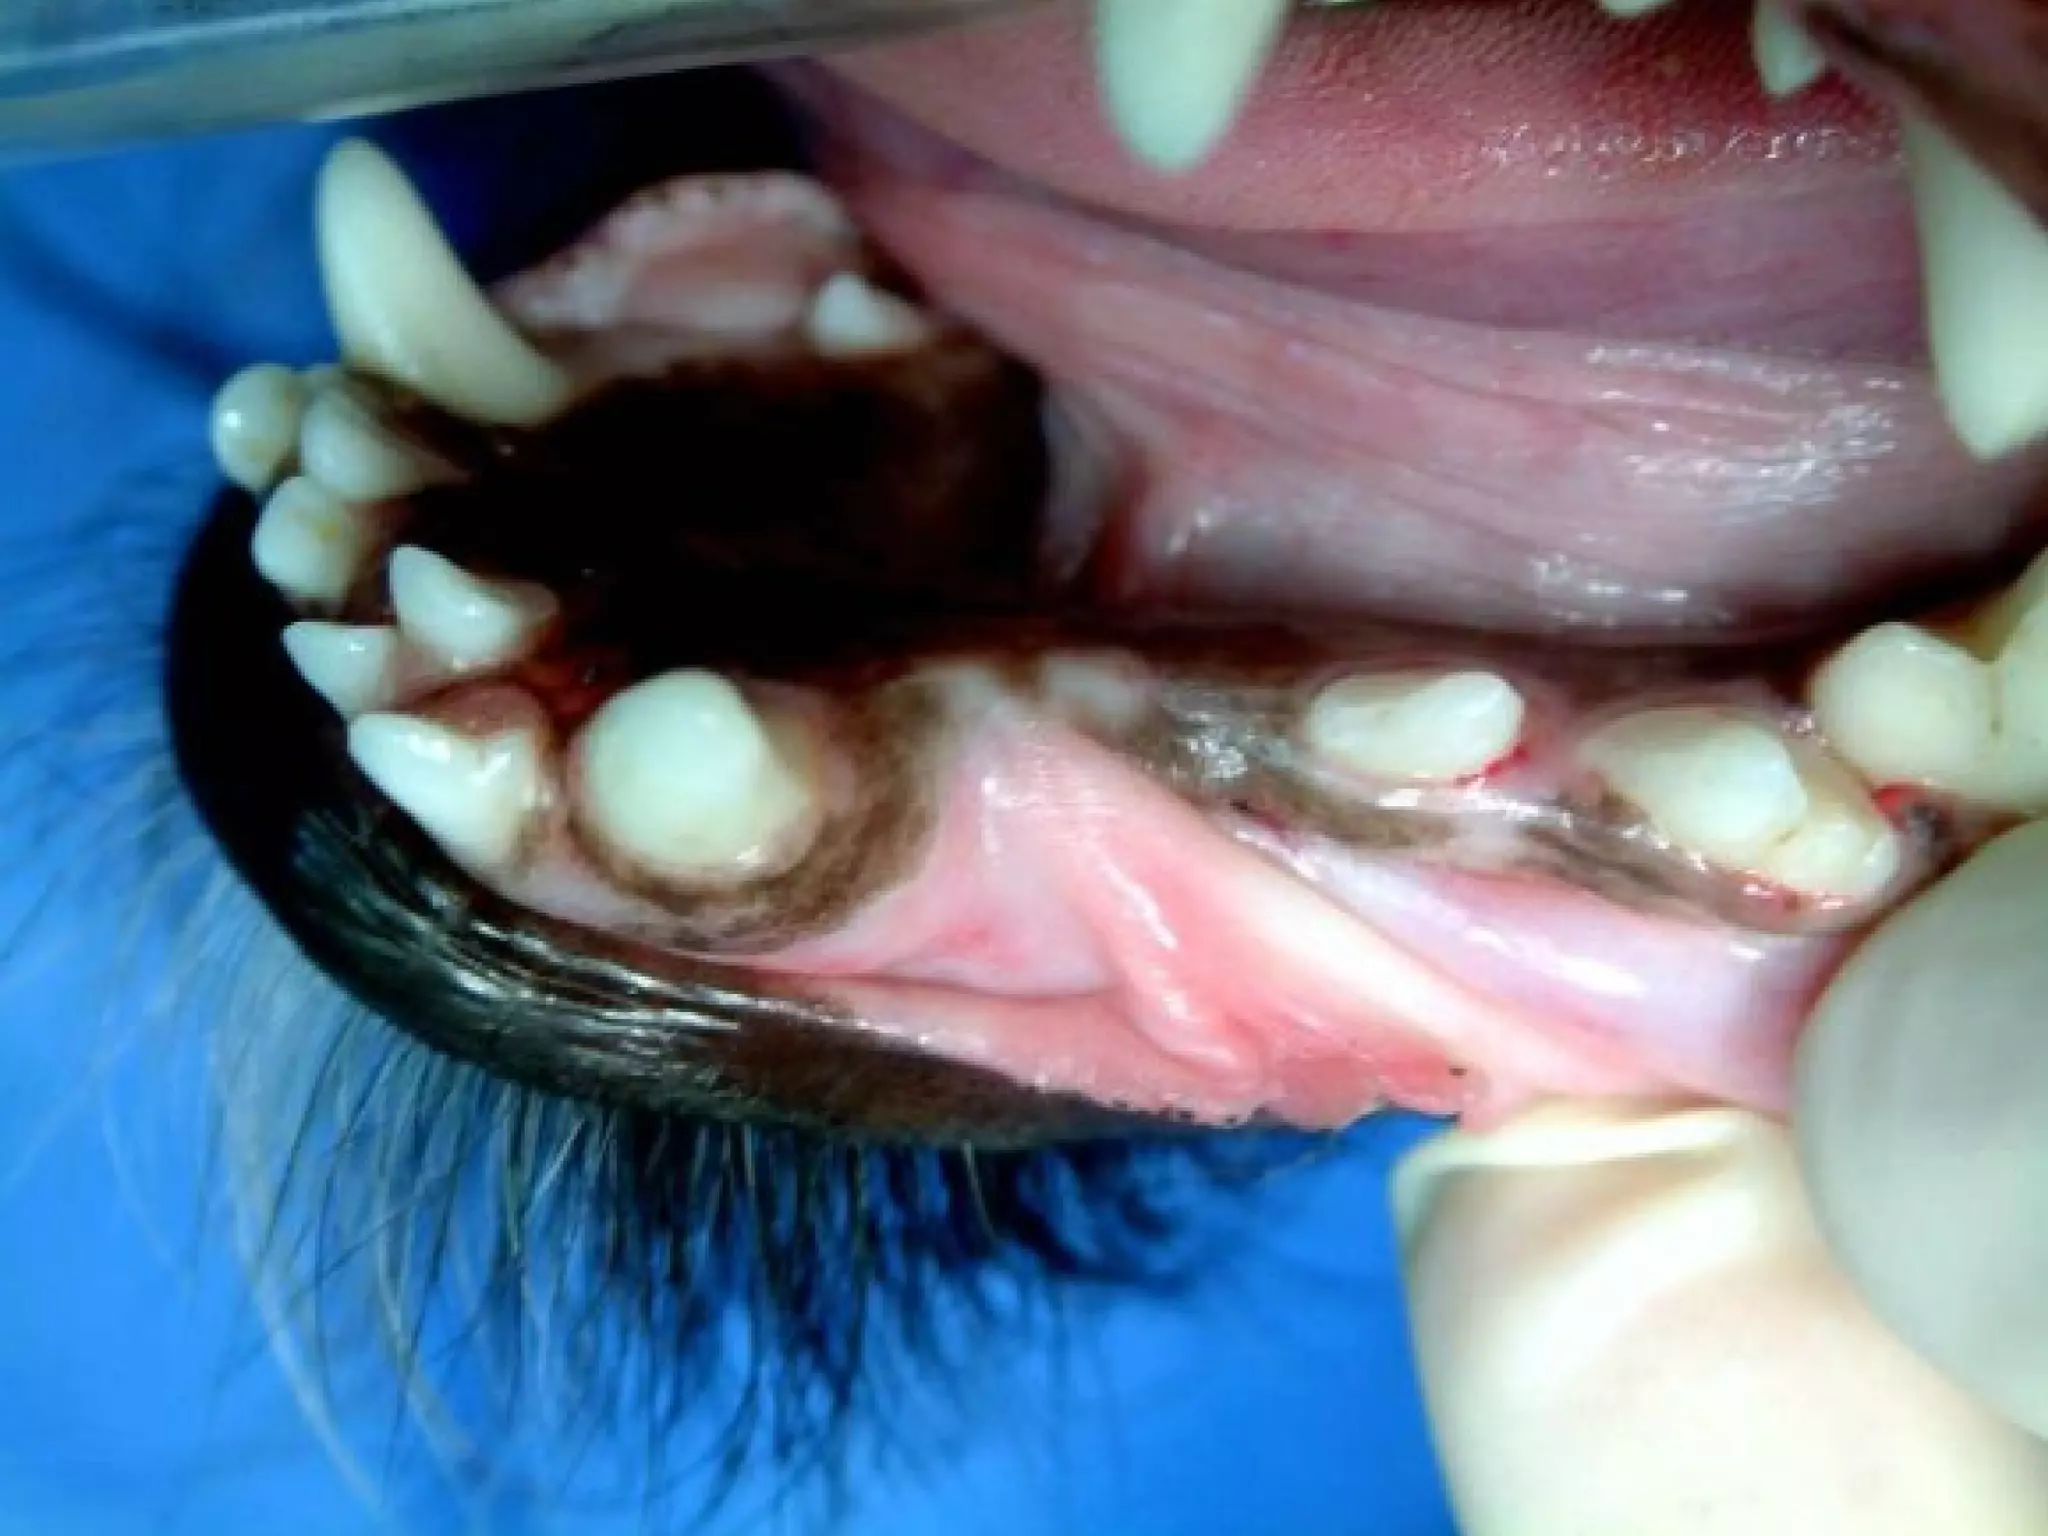

Take a look at the left mandible on this cat.

Text

What is the most likely cause of this process

in this cat?

What is the only definitive treatment?

Take a lookat the left mandible on this cat. Text 20

What is themost likely cause of this process in this cat? What is the only definitive treatment? 21